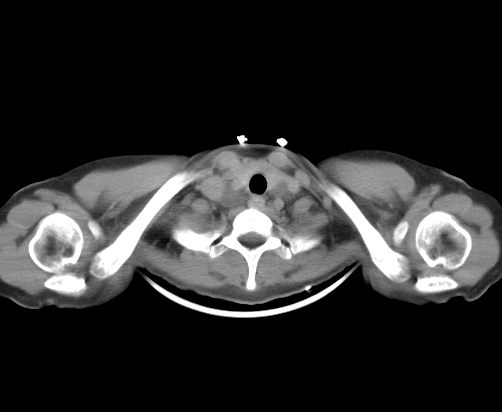

胸部